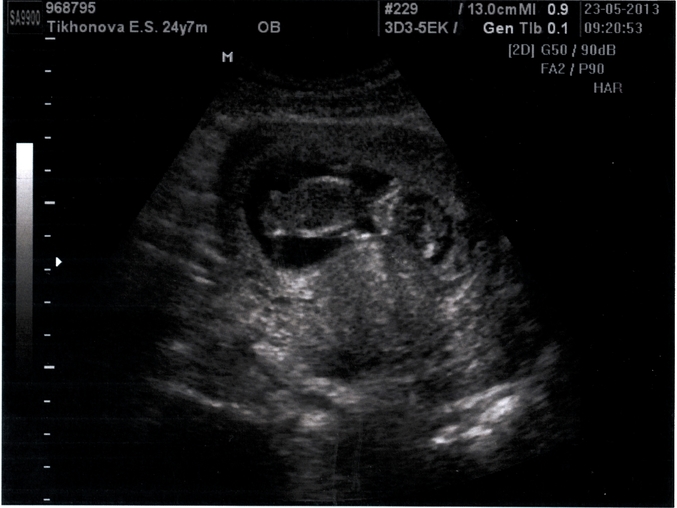

Ура! Свершилось!:)) Первое УЗИ. 12 нед. 6 дн.

Вот и случилось то , чего я так боялась и ждала одновременно - первое узи!)) Слава Богу, всё у нас хорошо! Акушерский срок 12 недель 6 дней

Копчико-теменной размер (CRL) = 6.26 cm

ЧСС = 146 уд/мин.

Толщина воротникового пространства = 1.6 mm

Длина бедра (FL) = 0.72 cm

Площадь сечения тела (FTA) = 3.51 cm2

Ариетальный размер головки (BPD) = 1.88 cm

Окружность живота (AC) = 6.64 cm

Ужас как переволновалась! Даже дышать тяжело было. ))) Малыш дрыгает ножками

Первый раз когда увидела, чуть не прослезилась! Правда потом , когда у меня наконец отлегло, он тоже видимо успокоился)) Отвернулся и не хотел показываться) По этому снимки получились не очень удачные.